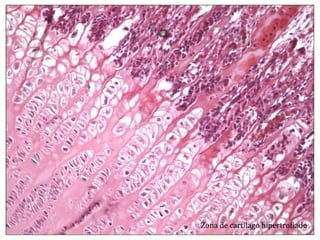

El documento describe diferentes aspectos de la histología del cartílago y el hueso, incluyendo las estructuras del cartílago como condroblastos, matriz y lagunas, y las estructuras óseas como conductos de Havers, osteoblastos y osteoclastos. También describe las etapas de la osificación endocondral, el proceso por el cual el cartílago se transforma en hueso, incluyendo las zonas de cartílago en reposo, proliferación, hipertrofia, erosión y osificación.